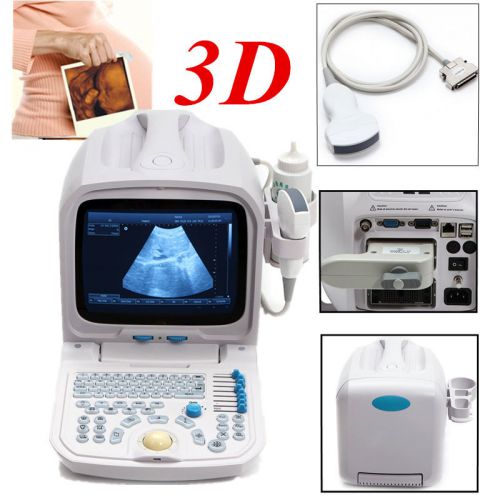

3D PC Plateform Based Full Digital Portable Ultrasound Scanner+3.5mhz convex pro

3D PC FULL digital Portable ultrasound scanner machine 3.5mhz Convex 3Y WARRANTY

Internal 3D 3.5mhz convex probe Portable Ultrasound Scanner machine warranty